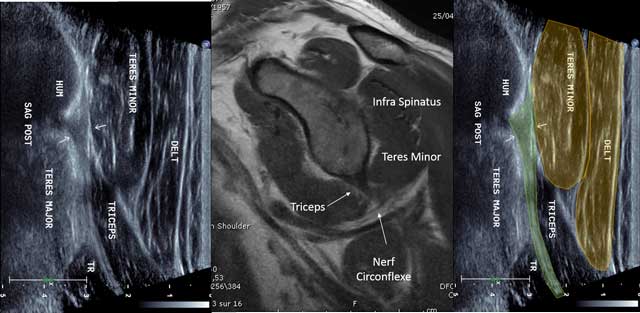

The long head of the Triceps Brachii originates in the infra-glenoid fossa of a short tendon [2]. The tendon is examined with the arm in abduction and external rotation (similar to the infra spinatus tendon). The analysis is made arms along the body in internal rotation or hand onto the contralateral shoulder. Sagittal cross sections provide lots of informations and the tendon appears to be short, hyper echoic and fibrillar (Figure 9). The probe is in the axis of the humerus searching for the lower side of the glenoid.

Figure 9

Sagittal view of the triceps tendon with MRI correlation. HUM: Humerus, TR: Triceps muscle, Nerf circonflexe: circumflex nerve.

In axial cross section, the tendon of the Triceps Brachii shows the lateral edge of the Velpeau Quadrilateral Space. Adjunct tendon bundles are not identifiable. The first layer shows the Teres Minor muscle and a small triangle with the fatty axillary nerve and posterior circumflex artery. The dynamic maneuvers with tricipital contraction make the difference between the long head of the Triceps Brachii muscle of the underlying Teres Major (Figure 10).

Figure 10

Sagittal view without (a) and with (b) Tricepscontraction with elbow in extension. TM: Teres Major, LT: long head of the triceps.